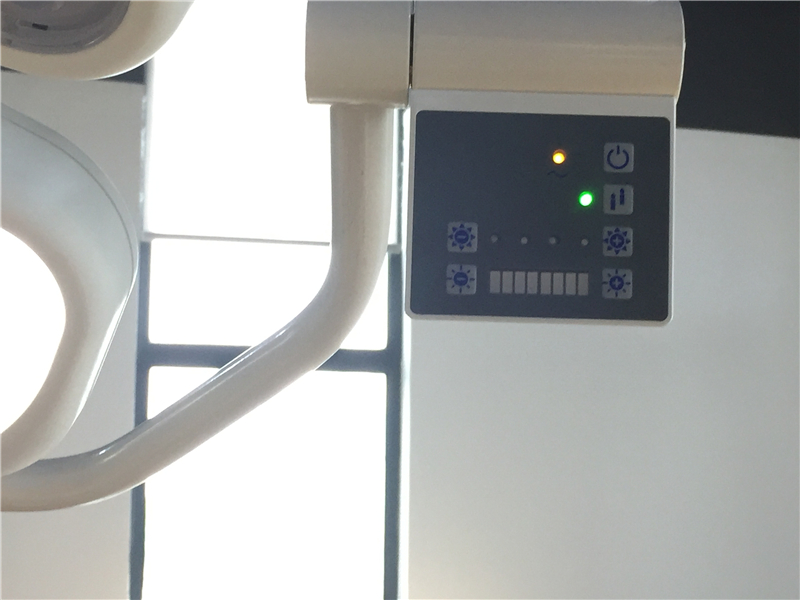

1. Full Digital Control

Compared to the analog control, it works more stable, flexible, accuracy, easier to use as well as longer lifespan.

5. PWM Low-Voltage Digital Continuous Dimming System

Luminance can be modulated range from 1% to 100% continuously.

8. Separated Control

Each bank can light up and dimming separately, every bank can be worked as a single viewer.

View Panel Luminance | PWM Dimming System, can be modulated range from 1% to 100% continuously, 3 inch LCD displayer, average Luminance :0~6000cd/ m2 | |||